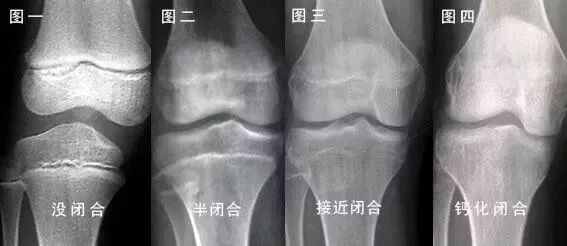

骺板(骨骺线)就是长高的关键

在长骨成熟以前

骺板不断地向着骨干生长和骨化

使长骨不断加长

骨骺闭合后

长骨便不再生长

这辈子都别做长高的梦了

如何才能知道自己的骨骺

到底有没有闭合呢?

看不懂没关系

看下图

不管成没成年

骨骺闭合才是长高的终结